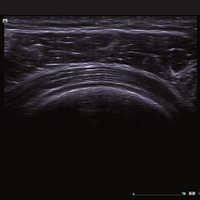

Das Ultraschallsystem Siemens ACUSON NX2 ist das mobile Einstiegssystem der nächsten Generation aus der Siemens ACUSON Produktlinie.

Als Mitglied der preisgekrönten Produktfamilie ACUSON NX verfügt die neue, sehr leichte und kompakte Plattform ACUSON NX2 über eine hochentwickelte Bildverarbeitungsarchitektur.

Sie bietet sowohl erstklassige Bildqualität auf dem größten Monitor ihrer Klasse als auch effiziente Workflows mit dem neuen taktilen Bedienfeld von Siemens. Das ACUSON NX2 eignet sich für eine Vielzahl von Untersuchungsverfahren im klinischen Alltag und ist die perfekte Wahl für die Standardbildgebung mit einem sehr guten Preis-Leistungsverhältnis.

Hochsensitive Breitbandschallköpfe unterstützen die MultiHertz™-Multifrequenzbildgebung und ermöglichen dem Benutzer eine optimale Kombination aus Bildauflösung, Eindringtiefe und Empfindlichkeit.

Das Siemens ACUSON NX2 Ultraschallgerät ist ein auf Performance optimiertes Ultraschallsystem, welches eine durchdachte Lösung für eine Vielzahl an Anforderung bietet und eine optimale Leistung erbringt. Das Ultraschallgerät ist hochgradig produktiv und effizient und liefert zuverlässige Ergebnisse. Das ACUSON NX2 ist darauf ausgelegt, die besonderen Herausforderungen des klinischen Praxisalltags zu erfüllen, und die Erwartungen des Anwenders zu übertreffen. Darüber hinaus liefert das ACUSON NX2 die neuesten Technologien, die es zu einem aufrüstbaren, skalierbaren und intelligenten Ultraschallsystem machen, welches konsistente und eindrucksvolle Ergebnisse liefert. Dank einem Höchstmaß an Spitzenleistung, wird eine große Diagnosesicherheit erzielt, und ihre Bildgebungstandards werden auf ein neues Niveau geführt.

Siemens ACUSON NX2: intelligentes und modernes Design

Das ACUSON NX2 Ultraschallsystem besitzt eine zukunftsfähige digitale Plattform mit nahezu unerreichter Bildqualität und sorgt für effiziente und zuverlässige Diagnosedaten. Die Vielseitigkeit des Ultraschallsystems wird mit einem großen kompatiblen Portfolio an Schallköpfen gedeckt, und so ist für jeden Anwendungsbereich etwas dabei. Die Bedienkonsole ist intuitiv aufgebaut und optimiert und erlaubt bis zu vier nach vorne gerichteten Schallkopfanschlüssen für eine enorme Effizienz und schnellen Workflow. So lassen sich bei der fetalen Bildgebung außergewöhnlich detailgetreue Darstellungen des Fetus im Gesicht zeigen oder durch die herausragende Farbdopplersensitivität bei der Darstellung der kleinen Gefäße des zystischen Schilddrüsenknotens kleinste Details erkennen. Weiterhin besticht das NX2 mit einfacher Aufrüstbarkeit bei wachsenden Anforderungen für Ihre zukünftigen Anwendungen und kompatible skalierbare Schallköpfe verringern ihren Kapitaleinsatz um bis zu 31 %.